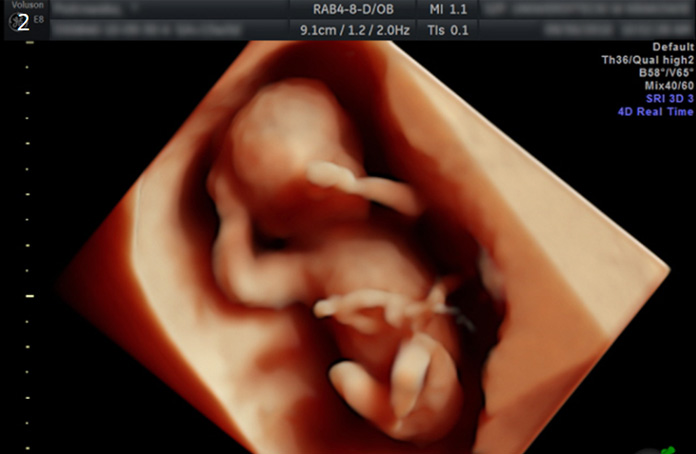

4D 입체영상초음파

입체영상초음파는 선택검사이며, 예약이 필요합니다. 태아의 얼굴, 손, 발, 척추 등이 가장 잘 보이는 임신 23-28주 사이에 실시하여 실물과 유사한 사진을 얻어 미리 아가를 만나볼 수 있는 검사입니다. 우리산부인과는 보다 감각 있는 사진을 위하여 초음파 "GE HD live "을 사용하고 있습니다.